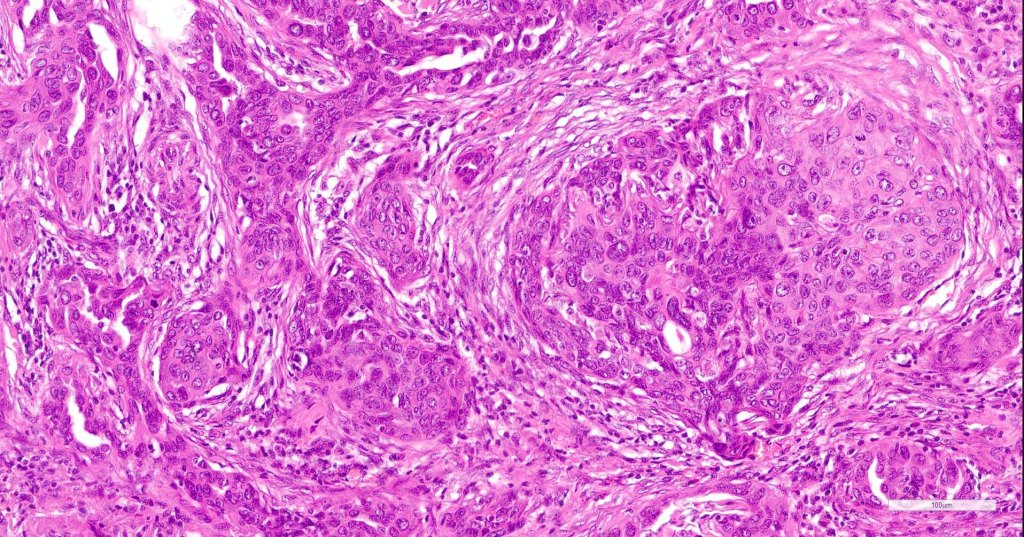

•Widely infiltrating biphasic tumor

•Superficial SCC

•Adenocarcinoma in deeper reaches

•Deep part may show both ducts and glands

•Often extends to the subcutaneous fat

•Perineural infiltration is commonly seen